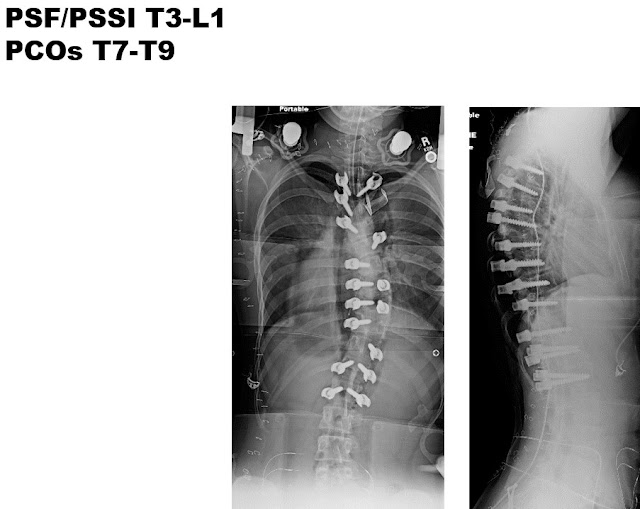

In order to maximize 3-dimensional correction and long-term outcome, while minimizing need for any additional surgeries the plan was to do a T3 to L1 posterior spinal fusion. T7-T8 and T8-T9 PCOs, or posterior column osteotomies were also performed. These osteotomies (PCOs) are done at the time of surgery to increase spine flexibility in all 3 planes, to maximize spinal deformity correction to as close to “normal” as we can safely achieve.

Pedicle screw are the optimal method of spine fixation. They allow rigid fixation to the spine, and permits the spine to be moved 3-dimensionally. Not every vertebra needs to have 2 screws. Strategically placing screws to optimize immediate correction and assure long-term outcome is preferred, so about 1.5 screws per level is common.

By placing the screws at certain locations, specifically at the apex, the spine can be derotated back more toward normal.

These postoperative radiographs are one year after surgery. The patient is nicely balanced 3-dimensionally and has nicely improved.